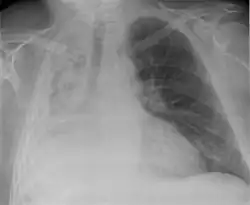

| Atelectasis of a person's right lung | |

Clinically significant atelectasis is generally visible on chest X-ray; findings can include lung opacification and/or loss of lung volume. Post-surgical atelectasis will be bibasal in pattern. Chest CT or bronchoscopy may be necessary if the cause of atelectasis is not clinically apparent. Direct signs of atelectasis include displacement of interlobar fissures and mobile structures within the thorax, overinflation of the unaffected ipsilateral lobe or contralateral lung, and opacification of the collapsed lobe. In addition to clinically significant findings on chest X-rays, patients may present with indirect signs and symptoms such as elevation of the diaphragm, shifting of the trachea, heart and mediastinum; displacement of the hilus and shifting granulomas.[13]